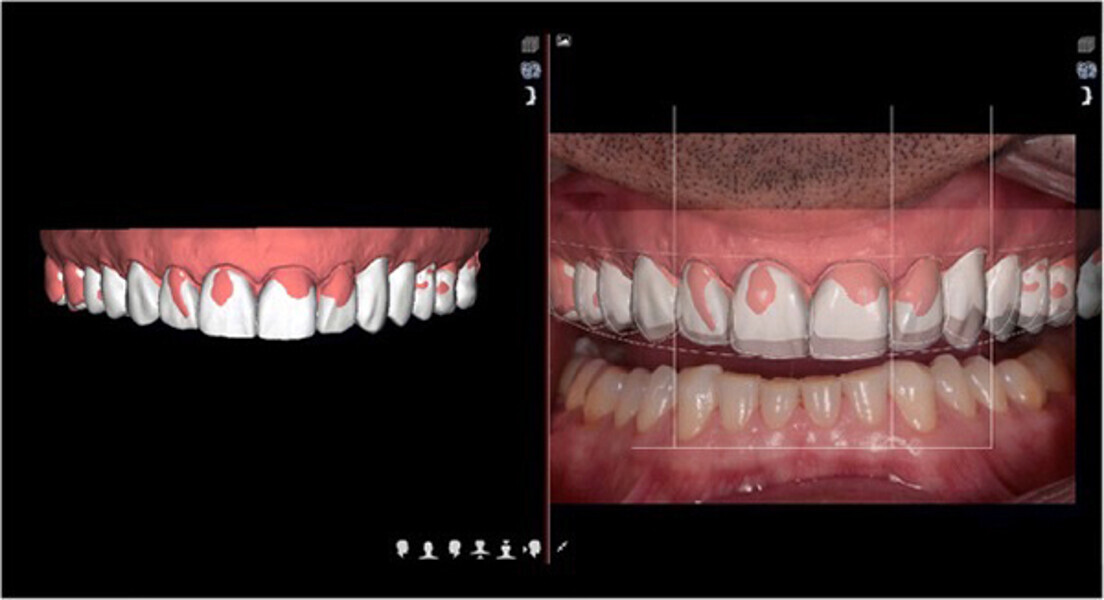

Fig. 11. Planificación del Diseño Digital de Sonrisa.

Fig. 12. Carillas y coronas finales preparadas digitalmente con el software de diseño Ceramill Mind y producidas en una fresadora (Ceramill Motion 2) a partir de bloques de cerámica de disilicato de litio mecanizables (VITABLOCS TriLuxe forte).